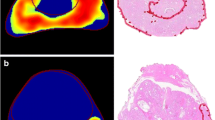

All multiparametric prostate MRI examinations were performed according to PI-RADS v2 guidelines [1] on a 3.0-Tesla magnet (Skyra, Siemens Healthcare, Erlangen, Germany) without an endorectal coil. The in-training technologists and radiologists reviewed the PI-RADS v2 guidelines [1] prior to initiating the quality assurance program. As the program progressed, iterative improvements in scan technique were implemented. The following sequences were acquired: narrow field-of-view (prostate) multiplanar (sagittal, axial, coronal) 2D T2-weighted turbo spin echo, narrow field-of-view (prostate) axial 3D T2-weighted turbo spin echo, narrow field-of-view (prostate) axial diffusion-weighted imaging with apparent diffusion coefficient map (b-values: 0, 400, 800, 1600 s/mm2), narrow field-of-view (prostate) axial dynamic contrast-enhanced imaging with a temporal resolution of 6–7 s, large field-of-view (whole pelvis) axial T1-weighted dual-echo gradient-recalled echo with Dixon reconstructions pre- and post-contrast. Dynamic contrast-enhanced imaging was obtained following the bolus administration (2 mL/s) of 0.1 mmol/kg gadobutrol (Gadavist, Bayer HealthCare Pharmaceuticals, Whippany NJ). The exact technical parameters of each sequence varied throughout the quality assurance effort as image quality was optimized.

The details of the study population are shown in Table 1. Median patient age was 68 years (IQR: 63–72), and median PSA was 6.8 ng/mL (IQR: 4.9–9.3 ng/mL). Most MRIs were performed in patients with an elevated PSA and negative prior biopsy(-ies) [42% (105/249)] or in those with low-risk prostate cancer being considered for active surveillance [36% (89/249)] (Table 1, Fig. 1). Image quality was significantly (p < 0.001) more likely to be impaired or non-diagnostic in the first three months (Fig. 2). Seven examinations [3% (7/249); 6 in months 1–6, 1 in months 7–12] were not assigned a PI-RADS v2 score because they were performed following local therapy (Table 1).

The 12-month longitudinal long-distance quality assurance program presented here is an example of how academic and private facilities without an official relationship can partner to promote high-quality imaging, interpretation, and patient care during the adoption of a new complex imaging technology. Based on our experience, a mentoring period of approximately 6 months encompassing at least 150 MRIs (~ 50 MRIs/radiologist) is recommended for radiology practices interested in developing a new prostate MRI program. The primary weaknesses of the in-training site during the first 1–6 months were image quality impairment and false-negative examinations. Through iterative improvement of image quality and mentored case review, we saw substantial improvements in image quality, inter-rater agreement, and diagnostic accuracy. In months 7–12, when only PI-RADS ≤ 2 and ‘difficult’ cases were reviewed, the false-negative results for Gleason ≥ 7 prostate cancer were 4% (4/89) overall, and only 1% (1/67) for the radiologists who participated for the entire relationship. The decline in maximum PI-RADS v2 score agreement observed in quarter 4 [ICC: 0.39 (0.11–0.61)] is likely multifactorial; it is probably related to a combination of adding a fourth in-training radiologist and restricting case review to only ‘difficult’ and PI-RADS ≤ 2 examinations.